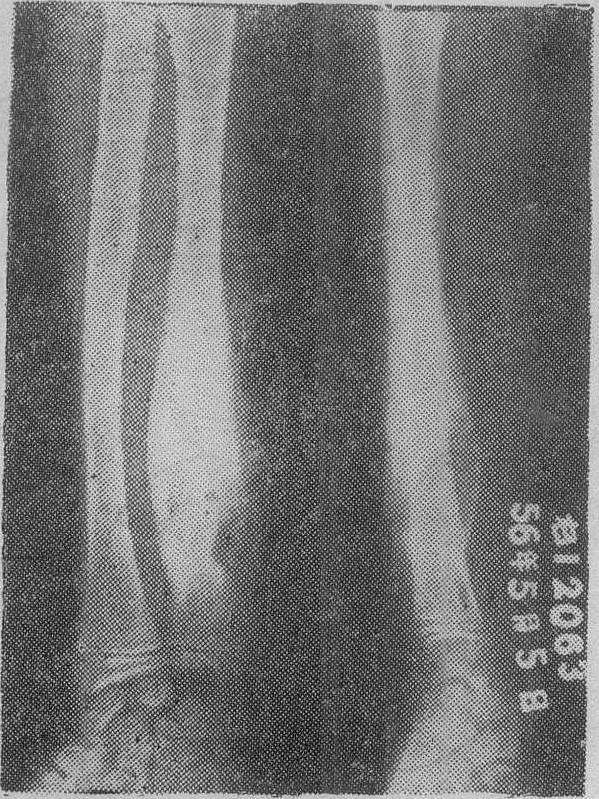

X线检查对本病非常重要。松质骨中心型结核早期可见局部骨小梁模糊是谓磨砂玻璃样改变,稍晚可见死骨游离,死骨一般呈椭圆形,密度比周围骨质稍高。死骨吸收后可见骨空洞,洞壁骨质稍致密(图1)。松质骨边缘型结核可见局限性溶骨性破坏,局部多无死骨或仅有细碎死骨,缺损边缘稍致密。密质骨结核可见髓腔内溶骨性破坏和骨膜新骨形成(图2)。干骺部结核则兼备松质骨和密质骨结核的特点(图3)。长期混合感染则骨质明显硬化。单纯滑膜结核仅见骨质疏松和局部软组织肿脓。早期全关节结核除局部骨质疏松和软组织肿胀外,尚可见关节小部分模糊或破坏。晚期全关节结核则关节边缘大部分模糊、破坏,关节间隙狭窄或消失,常合并脱位或畸形。除上述骨与关节改变外,有时尚能见到寒性脓肿影象,晚期脓肿可发生钙化。

图2 尺骨干密质骨结核可见多处溶骨性破坏及骨膜新骨形成